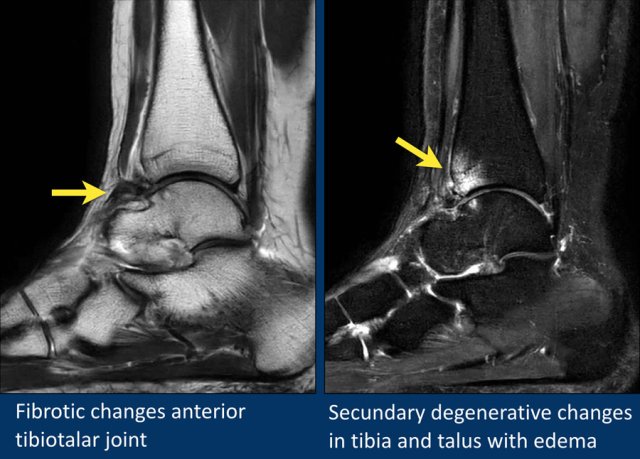

In this case there is fibrous thickening of the capsule (arrow).

This patient has secundary degenerative changes in the joint with subchondral edema and cyst formation.

It is a result of repetitive impaction of the fibrotic tissue on the bone during dorsal flexion.